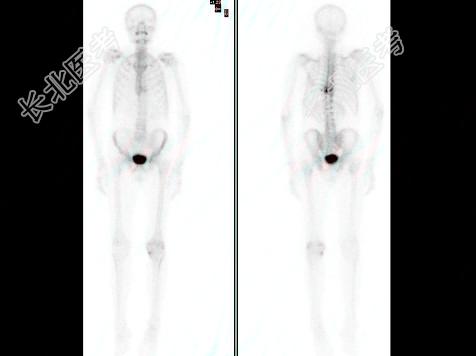

多项选择题男,68岁, 胸背痛3个月入院,行Tc-MDP全身骨显像、局部断层骨显像+X线图像融合如图, 可能的诊断是 ( )

A、多发性骨髓瘤

B、胸9、10椎体良性压缩性骨折

C、胸9、10椎弓根受累,提示恶性病变

D、大致正常的骨影像

E、胸9、10骨转移可能性大